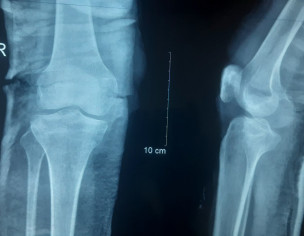

Talk to Orthopedic Surgeon on Knee Tibia Sprain Avulsion Fracture

Asking for Self, Female, 25 years old, Islamabad

Aoa 4 weeks before stairs se grne k vaja se fracture hva tha,boot slab lga h,but pain km n ho rahe, kindly xray check kr guide kr de,k kis qism ka fracture h,blood repot b h,

There is a fracture tibial spine appears to be undisplaced and it needs to be immobilized...if the pain is not improving you need to get checked by an orthopedic surgeon

tibial spine fracture. consult an orthopedist

tibial spine fracture and tlc count also increased in septic range

Agreed with other colleagues. Tibial spine fracture. For better evaluation of fracture and it's extent CT scan of the knee will be helpful.